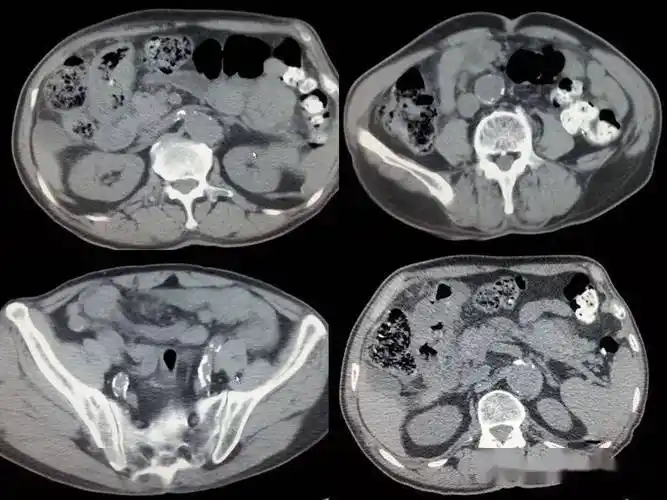

非同寻常的胃穿孔,最终诊断意想不到

消化道穿孔ct影像大汇总看完印象深刻

了腹部ct检查,发现了患者腹腔内存在游离气体,随即确诊为胃肠道穿孔